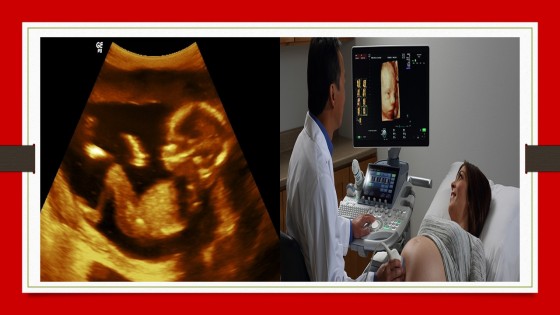

Sonography has advanced and turned into one of the most versatile ways for diagnosing and leading treatment of imperatively ill patients. It includes both cardiac (Echocardiography) and non-cardiac (lung, abdominal and vascular) ultrasound. With our exclusive sonography course online, you can obtain up-to-date lectures in prime areas from the leading practitioners and professionals in this field. As we provide both online and on-campus courses, you can easily choose the Online Ultrasound course for sonographers that you prefer and learn the concepts perfectly.

BilMed is a trusted ultrasound training institute, we make sure to teach the advanced techniques, utilization of unique tools and complete understanding of the ultrasound industry to the interested individuals who opt for our online courses. With our advanced abdominal ultrasound course, you can avail needed academic knowledge and clinical experience that will enable you to become a competent clinical practitioner. Also, your skills will be developed to critically review management options for a wide variety of frequent pathologies.

We offer you comprehensive training with hands-on experience facilitated by professionals in this domain. These ultrasonography courses will assist you in learning full knowledge and understanding of the safe utilization of ultrasound. Besides coursework, you will get access to the lab to recognize all the medical facility. We also provide you with excellent clinical placement opportunities and internship offers that will enhance your abilities and practical skills through our Online Ultrasound course for ultrasonologists.

By choosing ourgynaecology ultrasound course, you will learn to face the diagnostic challenges in daily routine clinical practices. Along with enhancing your theoretical knowledge in this field, we also make sure to focus on discussing and demonstrating different cases in order to learn the ways to use ultrasound in solving diagnostic issues in real clinical scenarios. We aim for the trainees who are willing to evolve their skills further to undergo advanced training in ultrasound training courses online.

With our well-crafted Online Ultrasound course for doctors, you can enhance your all the required aspects of radiology in order to become an expert in this field. We make sure to give highly engaging content to our students such as practical exercises and self-assessment questions, to strengthen your learnings and understandings related to our effective and certified Online Ultrasound course for radiologists to build your career swiftly.

In this course, students will learn how to recognize normal and abnormal abdominal scans. They will study regular pathologies that can be noticed with an abdominal sonogram. With our abdominal ultrasound course, you can grow and develop your techniques and knowledge with experts. During the lectures given by our professional staffs for Online Ultrasound course for doctors, special attention will be given to organ systems in the abdominal cavity such as liver, gall bladder, pancreas, GI tract, and others.